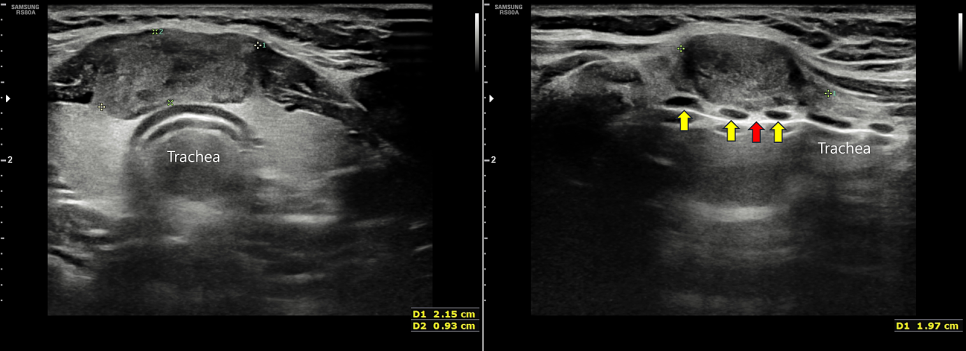

갑상선협부에 2센티미터 정도의 암의심결절이 있습니다.기도(기관, trachea)에 약간 붙어있는 것처럼 보이지만 오른쪽 사진을 보시면 기관연골(노란색 화살표) 사이로 들어간 부위(빨간 화살표)가 보이는데 연골과 결절(암 덩어리) 사이에 미세한 공간이 남아있어 기관연골 침범은 없는 것으로 보입니다.